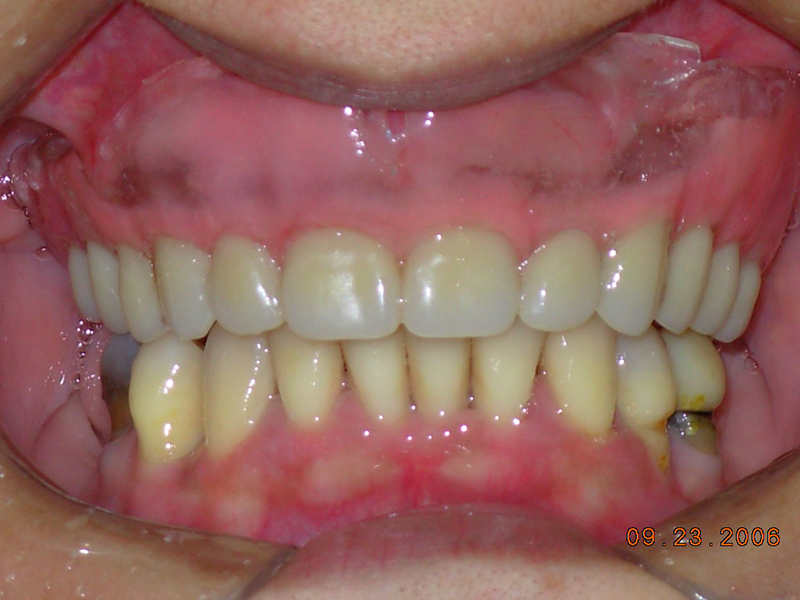

Na Clínica Pontes Odontologia, somos referência em implantes dentários em Fortaleza, oferecendo tratamentos de alta qualidade e tecnologia de ponta. Os implantes dentários são estruturas de titânio posicionadas cirurgicamente no osso maxilar ou mandibular para substituir as raízes dos dentes ausentes. Essa técnica permite a fixação de próteses personalizadas, restaurando a função mastigatória, a estética e a autoestima dos nossos pacientes.

Nosso compromisso é oferecer um tratamento de excelência, com profissionais especializados e tecnologia de última geração para implantes dentários em Fortaleza. Venha nos visitar e descubra por que a Clínica Pontes Odontologia é referência em implantes dentários em Fortaleza, devolvendo sorrisos e qualidade de vida aos nossos pacientes.